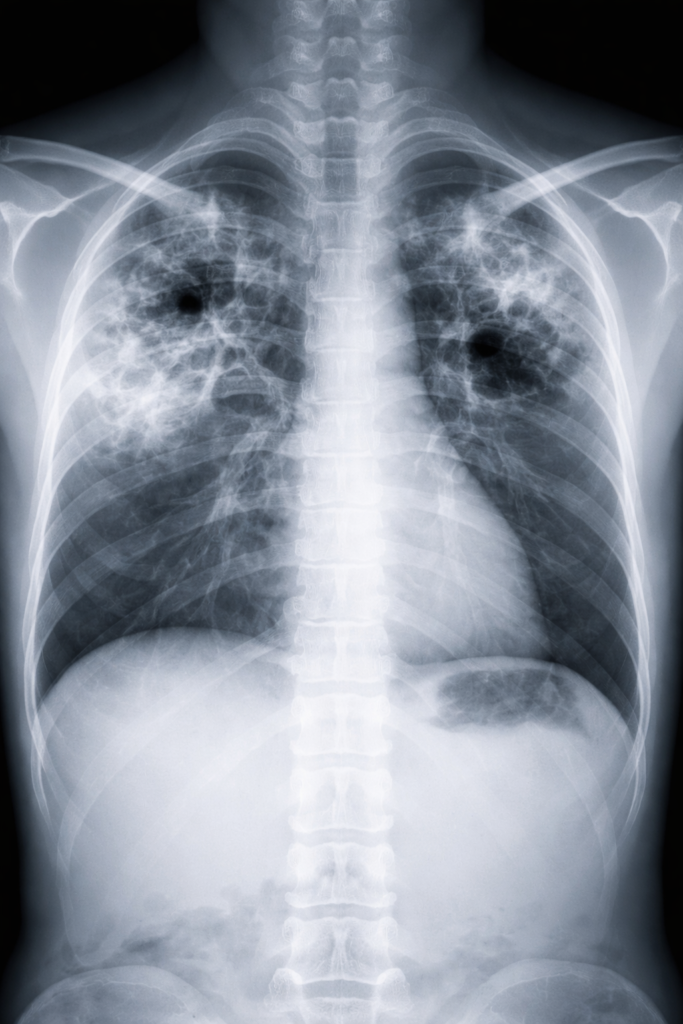

One key message of TB World Day is that tuberculosis is curable with proper treatment. Modern diagnostic tools have made TB detection faster and more accurate. Healthcare providers use various tests, including skin tests, blood tests, chest X-rays, and sputum tests to diagnose TB.

The World Health Organization has recently approved new near-point-of-care diagnostic tests that can provide results much faster than traditional methods. These innovations are particularly valuable in remote areas where access to laboratory facilities is limited. Rapid diagnosis means people can start treatment sooner, improving their chances of recovery and reducing transmission.

Artificial intelligence and machine learning are helping analyze chest X-rays more quickly and accurately, potentially identifying TB cases that human readers might miss. These technological advances complement traditional healthcare approaches, making diagnosis faster and more accessible to underserved populations.